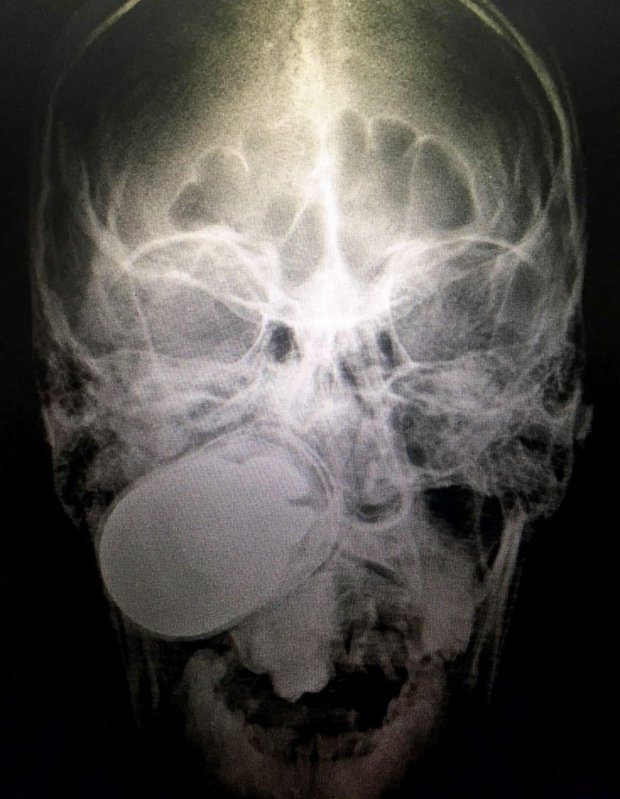

Yes, that is a live grenade lodged in the skull of a soldier.

Someone accidentally fired the explosive at Luis Eduardo Perez Arango’s face, according to EPA.

Colombian Military doctors had to carry out a risky operation to remove the grenade at a hospital in capital Bogota.